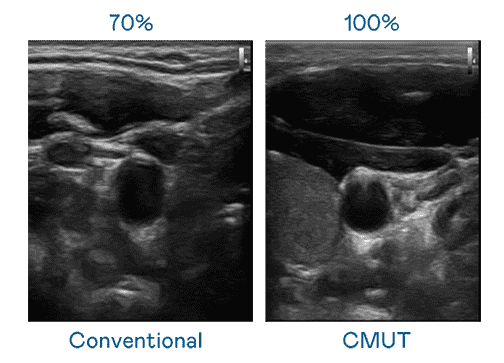

CMUT 技术是一种用电容式微机电元件来产生超音波讯号的技术。。。与传统 PZT 压电式技术相比,,,,CMUT 频宽增加 30%,,,,更宽频的超音波讯号让影像解析度大幅提升,,是实现高影像品质医疗超音波扫描、、促进精准医疗发展的关键技术。。。

大频宽带来超清晰影像

超音波影像的解析度高低,,,首先取决于探头能发出的讯号频宽。。。彩霸王 CMUT 可提供高清晰的超音波讯号,,,,提供高频宽、、、高灵敏度、、影像纹理细节更高的超音波影像,,,,协助医护人员缩短影像判读时间及利用精准的医疗影像进行诊断。。